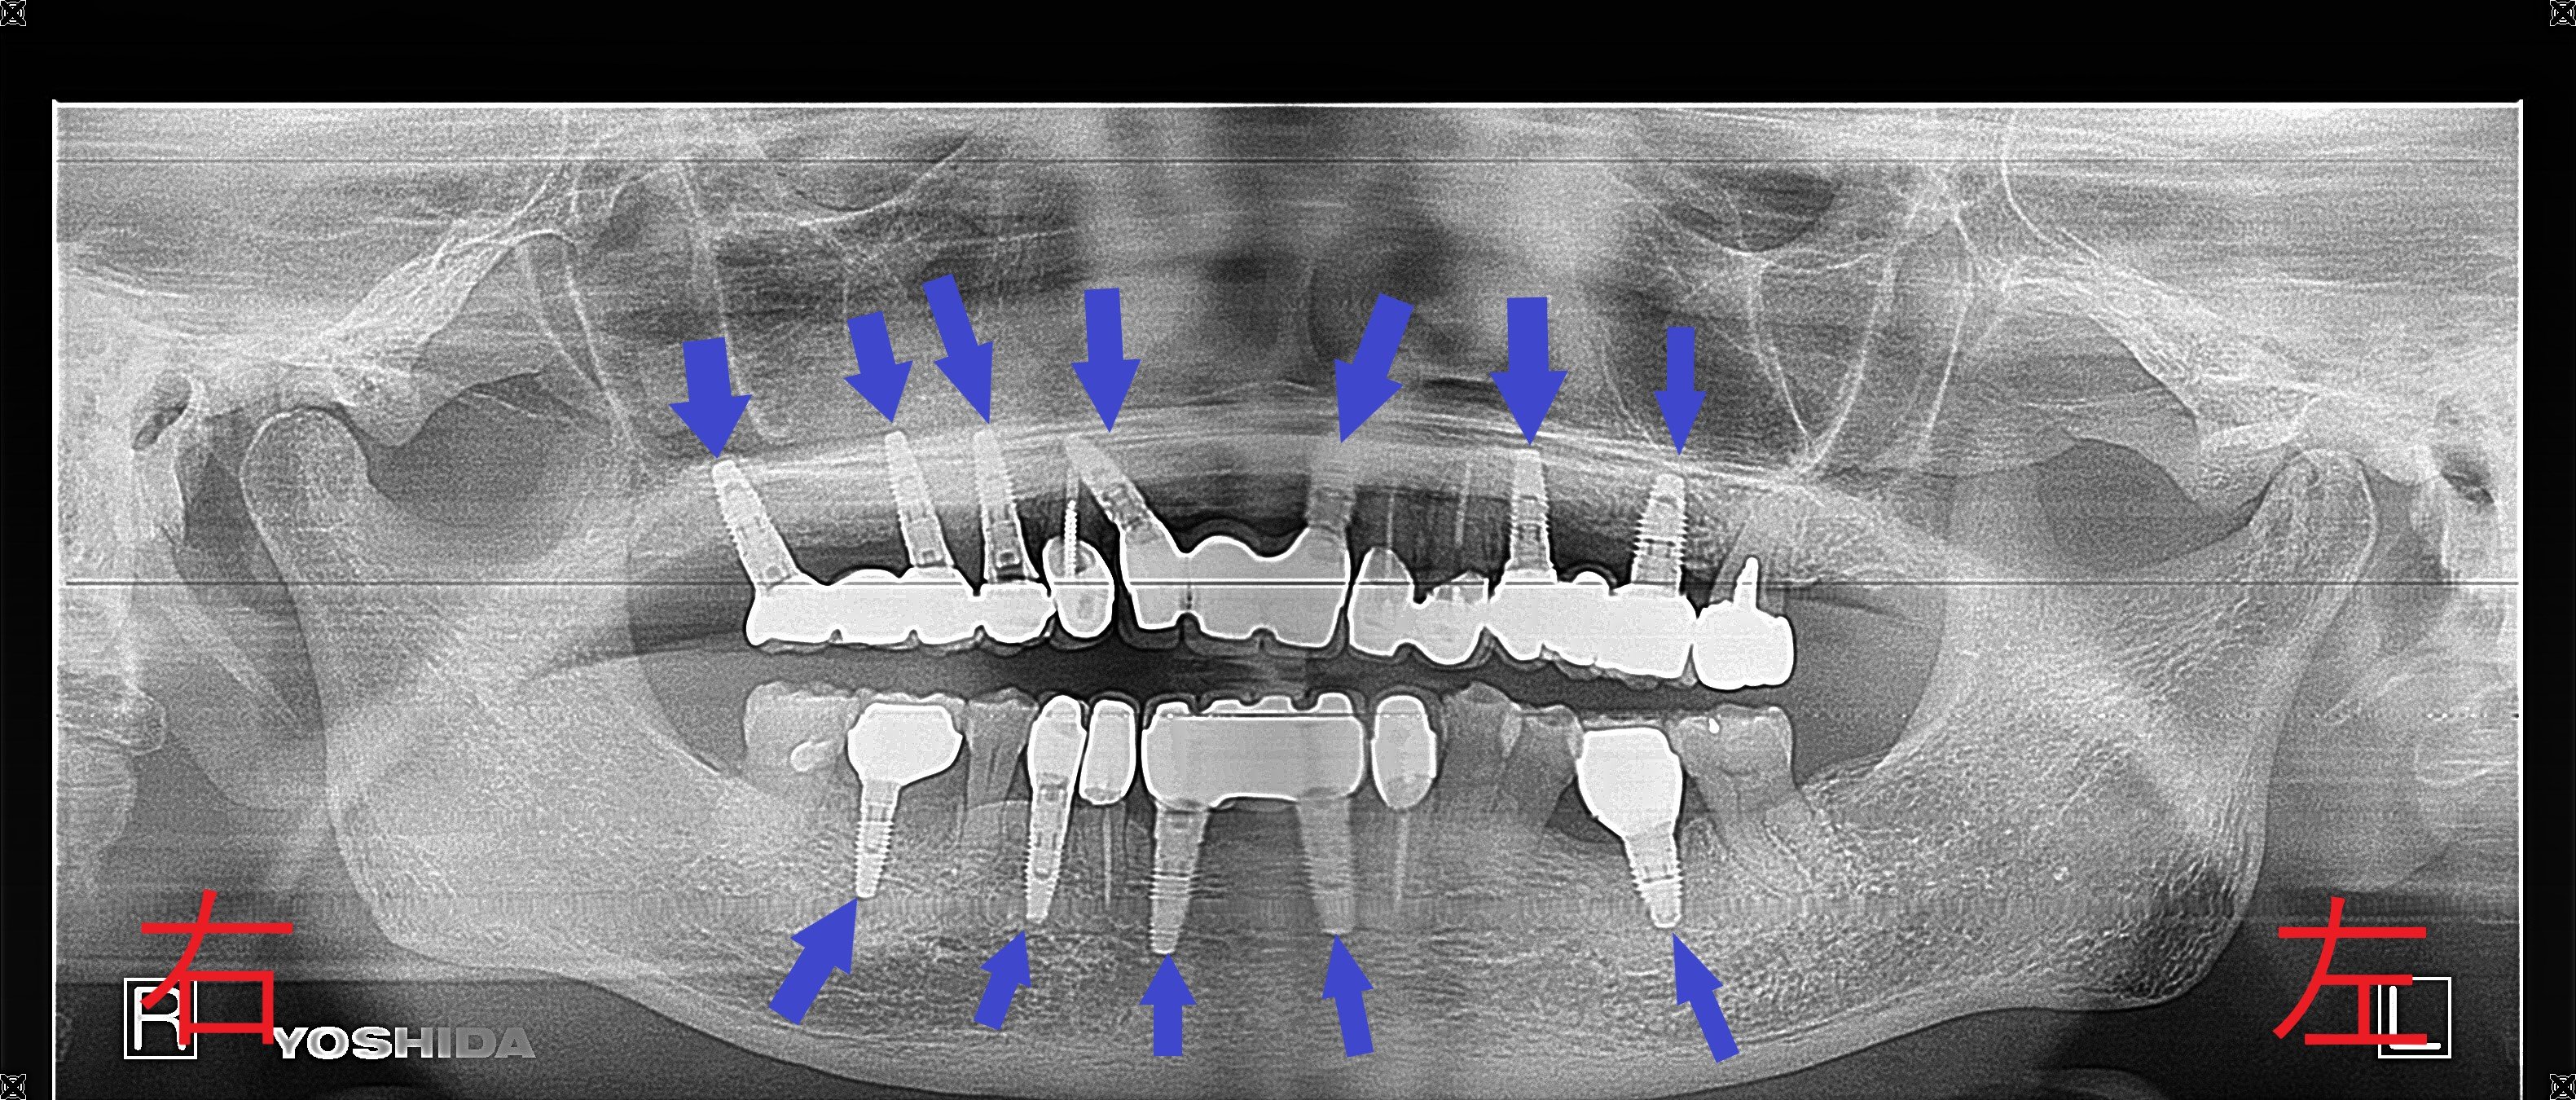

【インプラント埋入と最終補綴】

・上顎に7本、下顎に5本のインプラントを埋入(青色矢印)

・咬合平面の再構築を実施

・一部の天然歯(黄色矢印)は削合・神経除去なしで保存し、咬合関係を確保